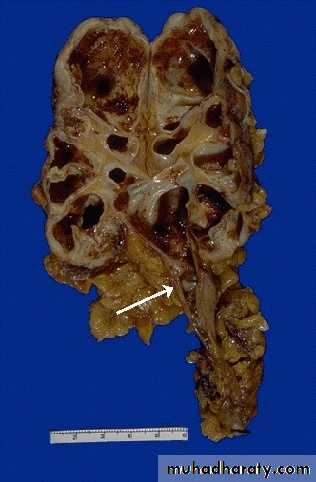

adult polycystic kidney showing enlarged kidney with multiple cysts different in size filled with serous or haemorrhegic fluid.